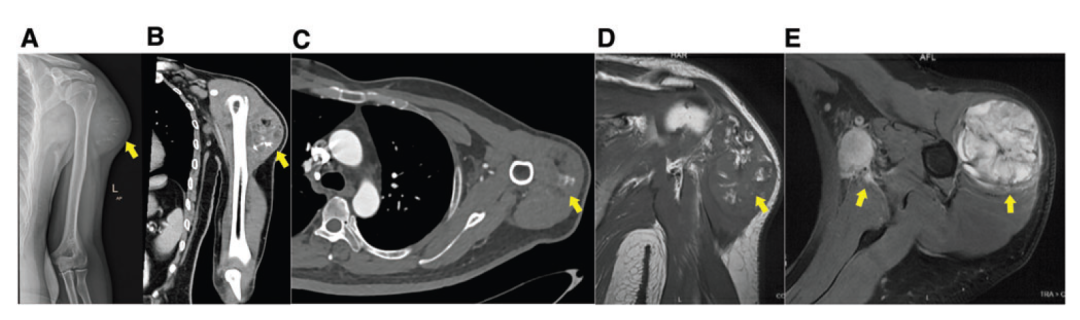

该2型糖尿病患者接受移植的β细胞是由自体 iPSC 分化而来,2020年6月,该患者在北京的某家医院接受了自体 iPSC 来源的β细胞的注射,病历显示,该患者血液中分离的体细胞被重编程为 iPSC,然后再分化为胰岛β细胞,在扩增后通过左上臂的三角肌注射到患者体内。到治疗后2个月,患者的血糖调节和胰岛素水平并没有改善,反而在注射位置出现肿块以及腋窝淋巴结肿大。

此后,这名患者来到了云南省肿瘤医院接受了治疗(该患者的iPSC治疗并非在云南省肿瘤医院进行)

磁共振成像(MRI)扫描提示,该肿瘤为良性或中间性肿瘤。2020年8月,患者接受了肿瘤切除手术,病理诊断显示是未成熟畸胎瘤PET-CT 检查显示存在同侧腋窝和颈部淋巴结转移。经过两个周期的常规化疗后,患者的肿瘤出现进展。此后患者接受了颈部和腋窝手术区的辅助放疗,并结合化疗。到2021年10月,PET-CT 显示患者没有出现肿瘤复发或远端转移。